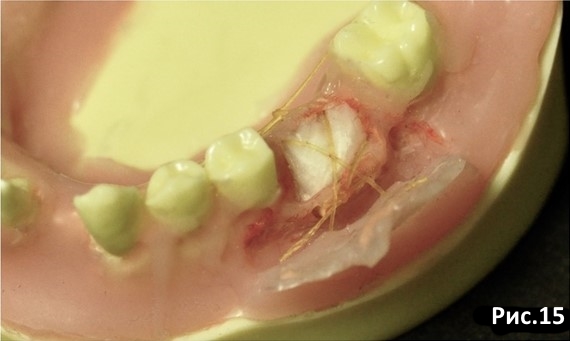

Фиксируем мембрану компрессионным крестообразным швом через надкостницу. Рис.15